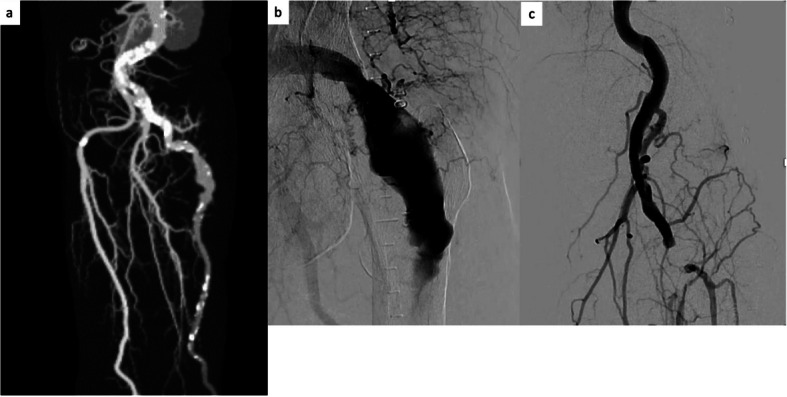

Case presentation: This case report details the treatment of two women (aged 89 and 82 years) with ALI associated with PSA. In both cases, reperfusion was achieved without CDT and stent grafts were deployed across the PSA aneurysm. The final angiogram showed that the PSA aneurysms had disappeared, and the vessel runoff was maintained. Both patients were successfully discharged from the hospital and experienced no complications over the next 6 months.